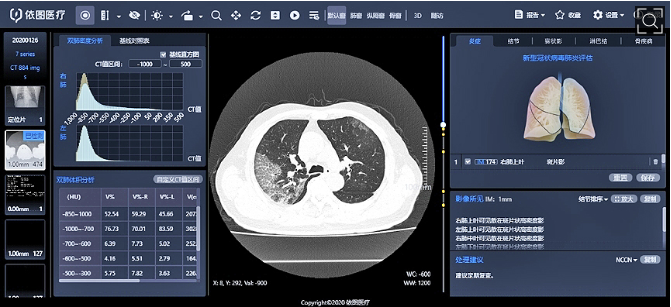

이투 헬스케어, 코로나 19 용 AI 흉부 스캐너 분석 시스템 현장 투입

- 코로나19 사례를 추적하고 분석할 수 있는 시스템

- 병변이 발견된 영역을 자동 감지(detection) 2~3초 내에 정량적인 분석을 시행함

- 이를 통해 폐 CT 이미지에 대한 분석을 실행하고, 바이러스로 손상된 폐에 대한 치료를 결정하도록 도움

- 현재 상하이 공중보건 클리닉센터에서 코로나 19 진단용 흉부 CT 지능화 평가 시스템을 지원하고 있음